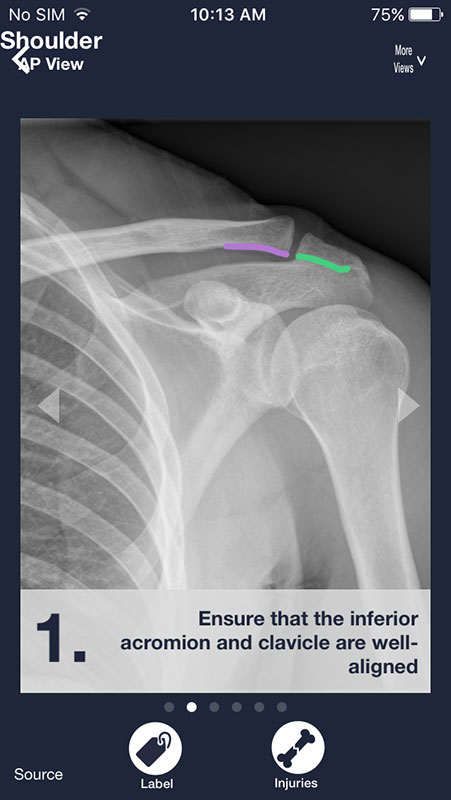

You can swipe the screen to navigate through the series of images. Each following image is annotated and contains a piece of advice on what to look for on a radiograph in order to distinguish between normal anatomy and abnormalities/pathologies.

There are two buttons below each image. First, Label button annotates the structures in the first image, showing them in different colors with names.